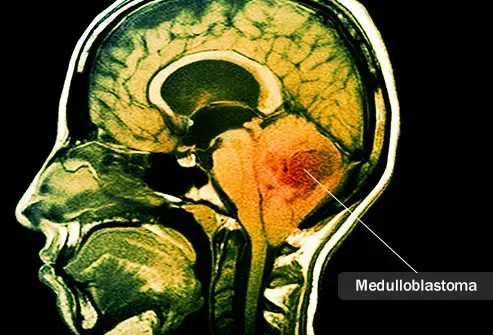

Менингиомите глиоми и глиобластоми са основните видове първични мозъчни тумори, но има и други. Те възникват от различни области в мозъка. Аденомите са тумори, които се появяват в хипофизната жлеза. Хордомите са първични мозъчни тумори, които се срещат в гръбначния стълб и черепа. Саркомите са първични мозъчни тумори, които възникват от Dura (меникс тъкан слой, който очертава хрущяла или костите на гръбначния стълб и черепа). Медулобластомите са първични мозъчни тумори, които възникват от малкия мозък, който е частта от мозъка в задната част на черепа.